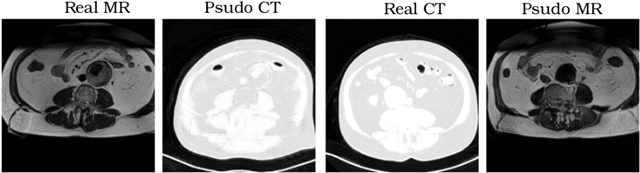

Abstract:Recently, the cycle-consistent generative adversarial networks (CycleGAN) has been widely used for synthesis of multi-domain medical images. The domain-specific nonlinear deformations captured by CycleGAN make the synthesized images difficult to be used for some applications, for example, generating pseudo-CT for PET-MR attenuation correction. This paper presents a deformation-invariant CycleGAN (DicycleGAN) method using deformable convolutional layers and new cycle-consistency losses. Its robustness dealing with data that suffer from domain-specific nonlinear deformations has been evaluated through comparison experiments performed on a multi-sequence brain MR dataset and a multi-modality abdominal dataset. Our method has displayed its ability to generate synthesized data that is aligned with the source while maintaining a proper quality of signal compared to CycleGAN-generated data. The proposed model also obtained comparable performance with CycleGAN when data from the source and target domains are alignable through simple affine transformations.